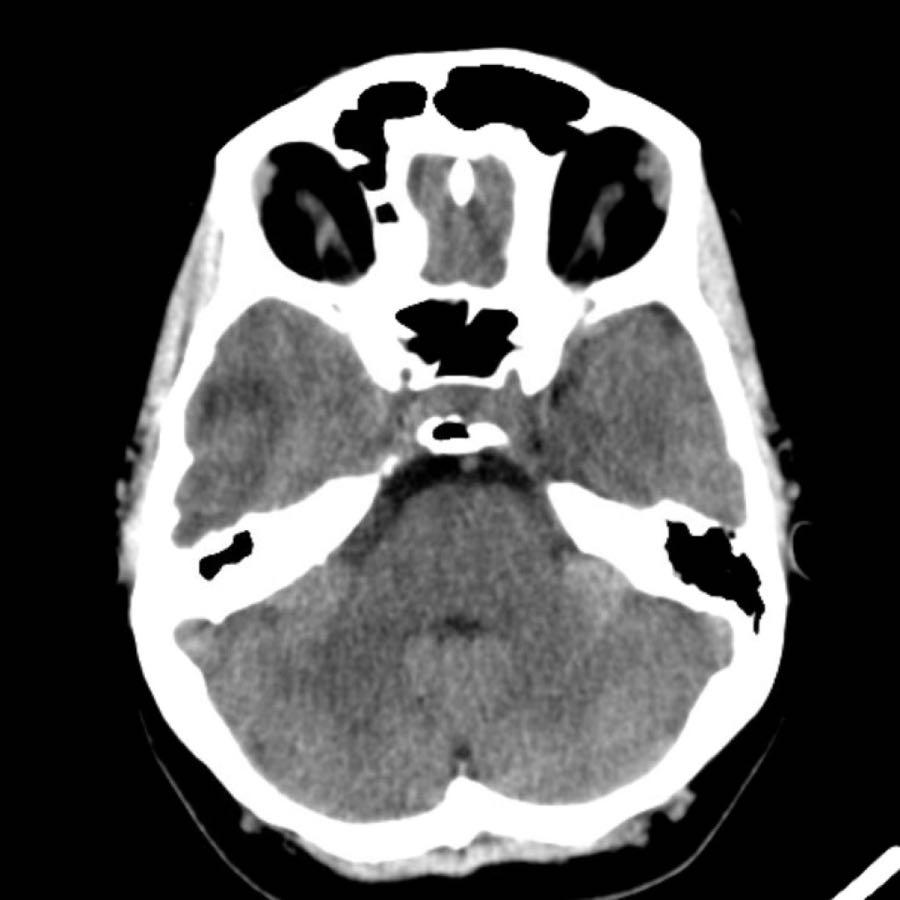

Các hình ảnh thuộc về một bệnh nhân nữ trẻ tuổi với triệu chứng đau đầu khởi phát đột ngột vài giờ sau khi sử dụng cocaine.

Bệnh nhân nhập viện với tình trạng liệt nửa người bên trái.

- A – NCCT cho thấy xuất huyết thùy não ở thùy đỉnh phải với lan rộng vào hệ thống não thất (chấm nhỏ tại lỗ Monroe).

- B – quan sát thấy các tĩnh mạch dẫn lưu lớn.

- C – mũi tên chỉ vào động mạch não giữa phải bị đẩy lên trên do hiệu ứng khối của khối xuất huyết.

- D – quan sát thấy một nidus nhỏ kết nối với các tĩnh mạch bất thường (khá khó nhìn thấy trên CT).